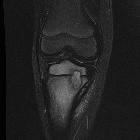

MRI

The “penumbra sign” on magnetic resonance (MR) imaging is useful for discriminating subacute osteomyelitis from other bone lesions. The penumbra sign is a rim lining of an abscess cavity with higher signal intensity than that of the main abscess on T1-weighted images with strongly and rapidly enhance after contrast.